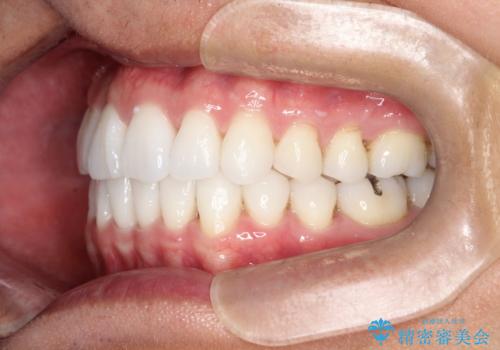

内側に入ってしまった前歯を正しい位置へ インビザライン矯正

右上の前から2番目の歯が引っ込んで、下の前歯にはガタガタがありました。

目立たずに矯正治療を終えることができたことに満足していただけました。